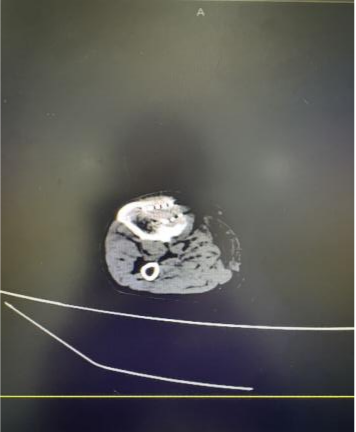

案例三:刘先生,65岁,右下肺占位(2.0*2.0cm)。2025年11月12日,在CT引导下行经皮肺病损微波消融术+肺穿刺术,11月19日病检回示为腺癌。

消融前                                                                              消融后